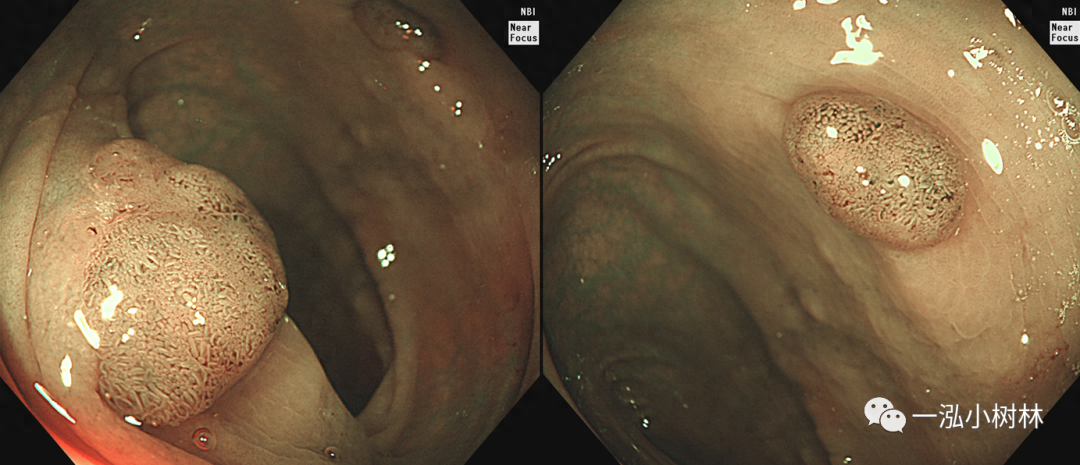

图1 结肠管状腺瘤(JNET2A型)